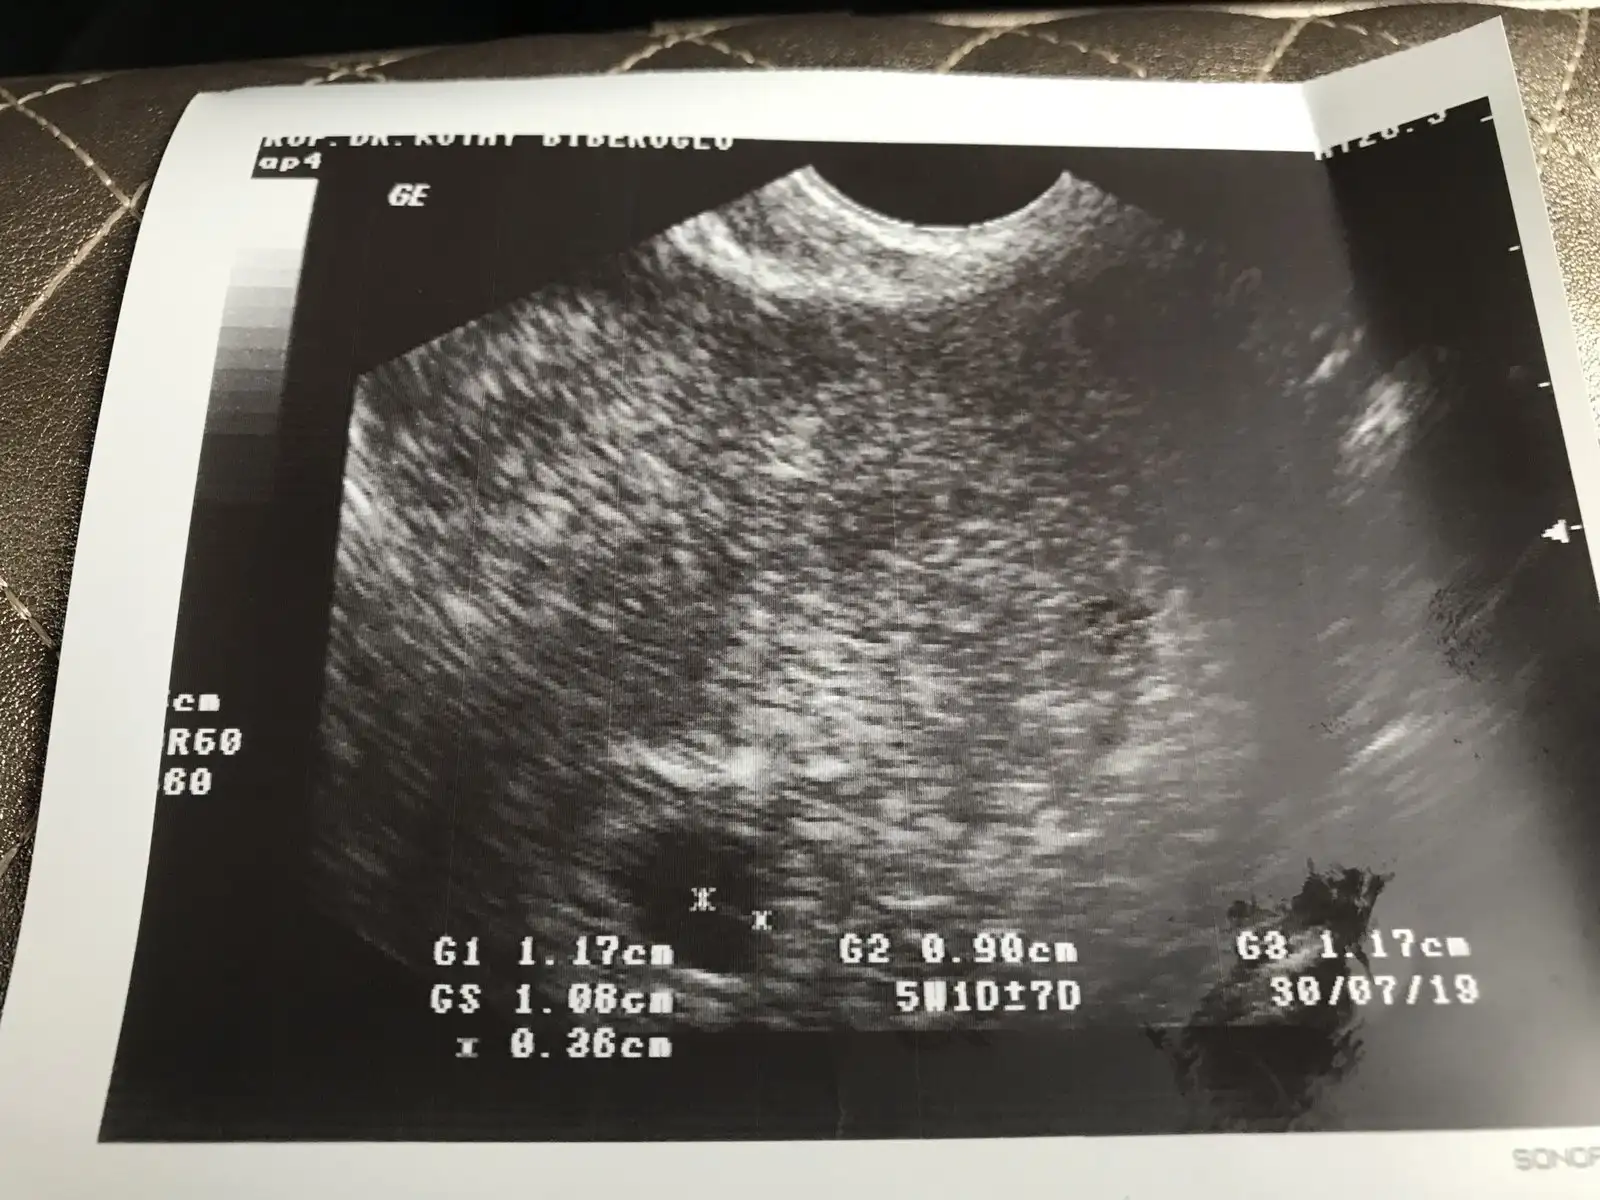

Sanmıyorum ovulasyon testi kullandım adetin 14 15 yumurtlama gunumdu bize adetime 3 gün varken evde gebelik testiyle öğrendim bende saskinim hayırlısı artık pazartesi tekrar gideceğim içimi rahatlatmak için herkese soruyorumGeç dollenme mi acaba sizin de